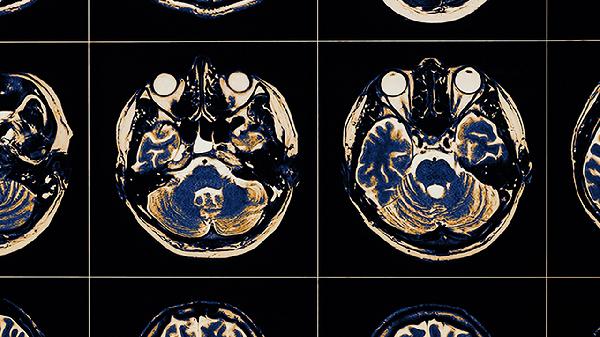

脑血栓片主要用于治疗缺血性脑血管疾病,如脑血栓形成、短暂性脑缺血发作、脑动脉硬化伴随的眩晕等症状。脑血栓片属于中成药,具有活血化瘀、通经活络的功效,可缓解因脑血管循环障碍引起的相关症状。

脑血栓片可用于脑血栓形成的辅助治疗。脑血栓形成通常与血管内皮损伤、血液高凝状态等因素有关,可能表现为肢体麻木、言语不清等症状。脑血栓片中的丹参、川芎等成分有助于改善脑部微循环。需遵医嘱联合阿司匹林肠溶片、华法林钠片等抗凝药物使用。